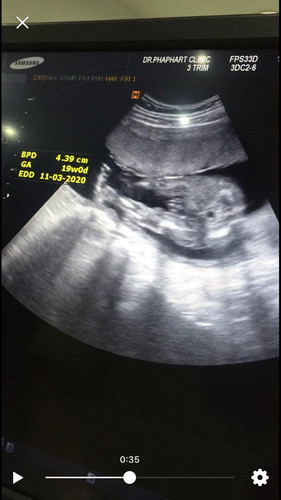

สอบถามแม่ๆค่ะ แบบนี้ผญ. หรือ. ผช. คะ

หมอบอกผญ. แต่เราเห็นเหมือนจู๋อะค่ะ55 สอบถามแม่ๆ แบบนี้ผญ.หรือผช. คะ

ดีที่สุดดูจากค่าโครโมโซม แต่บางทีการดูผลอัลตร้าซาวน์ก็คลาดเคลื่อนได้คะ ในอายุครรภ์น้อย

ถ้าให้ดูในรูป ยังไงก็ผู้ชายจ้าา ถ้าผู้หญิงมันจะไม่แหลมแบบนี้

น่าจะน้องผญ.นะคะ บ้านนี้ก็ผญ.เหมือนกัน เห็นเป็นร่องๆแบบนี้

เหมือนกันเหมือนค่ะหมอบอกผญ. แต่มันดูแหลมๆ

มีสองแคมน่าจะผู้หญิงค่ะ ถ้าผู้ชายต้องแบบนี้

เหมือนจะเห็นเปนกลีบค่ะ น่าจะผู้หญิงไหม

หมอก็บอกผญ. ค่ะ. 55 ขอบคุณนะคะ